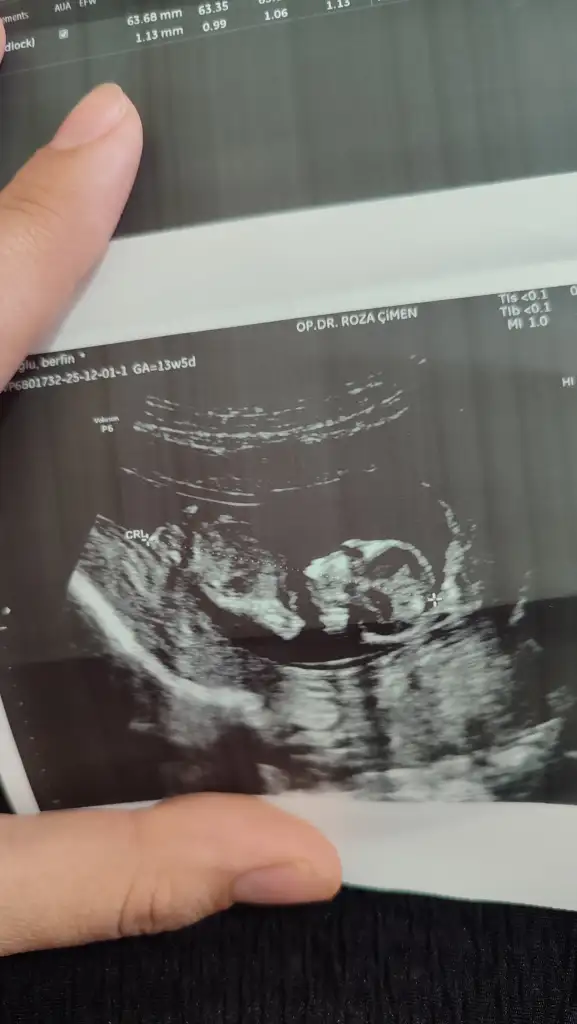

Cinsiyet tahmini yaparmısnz kızlar12+6gun

IMG_20251201_125919.webp